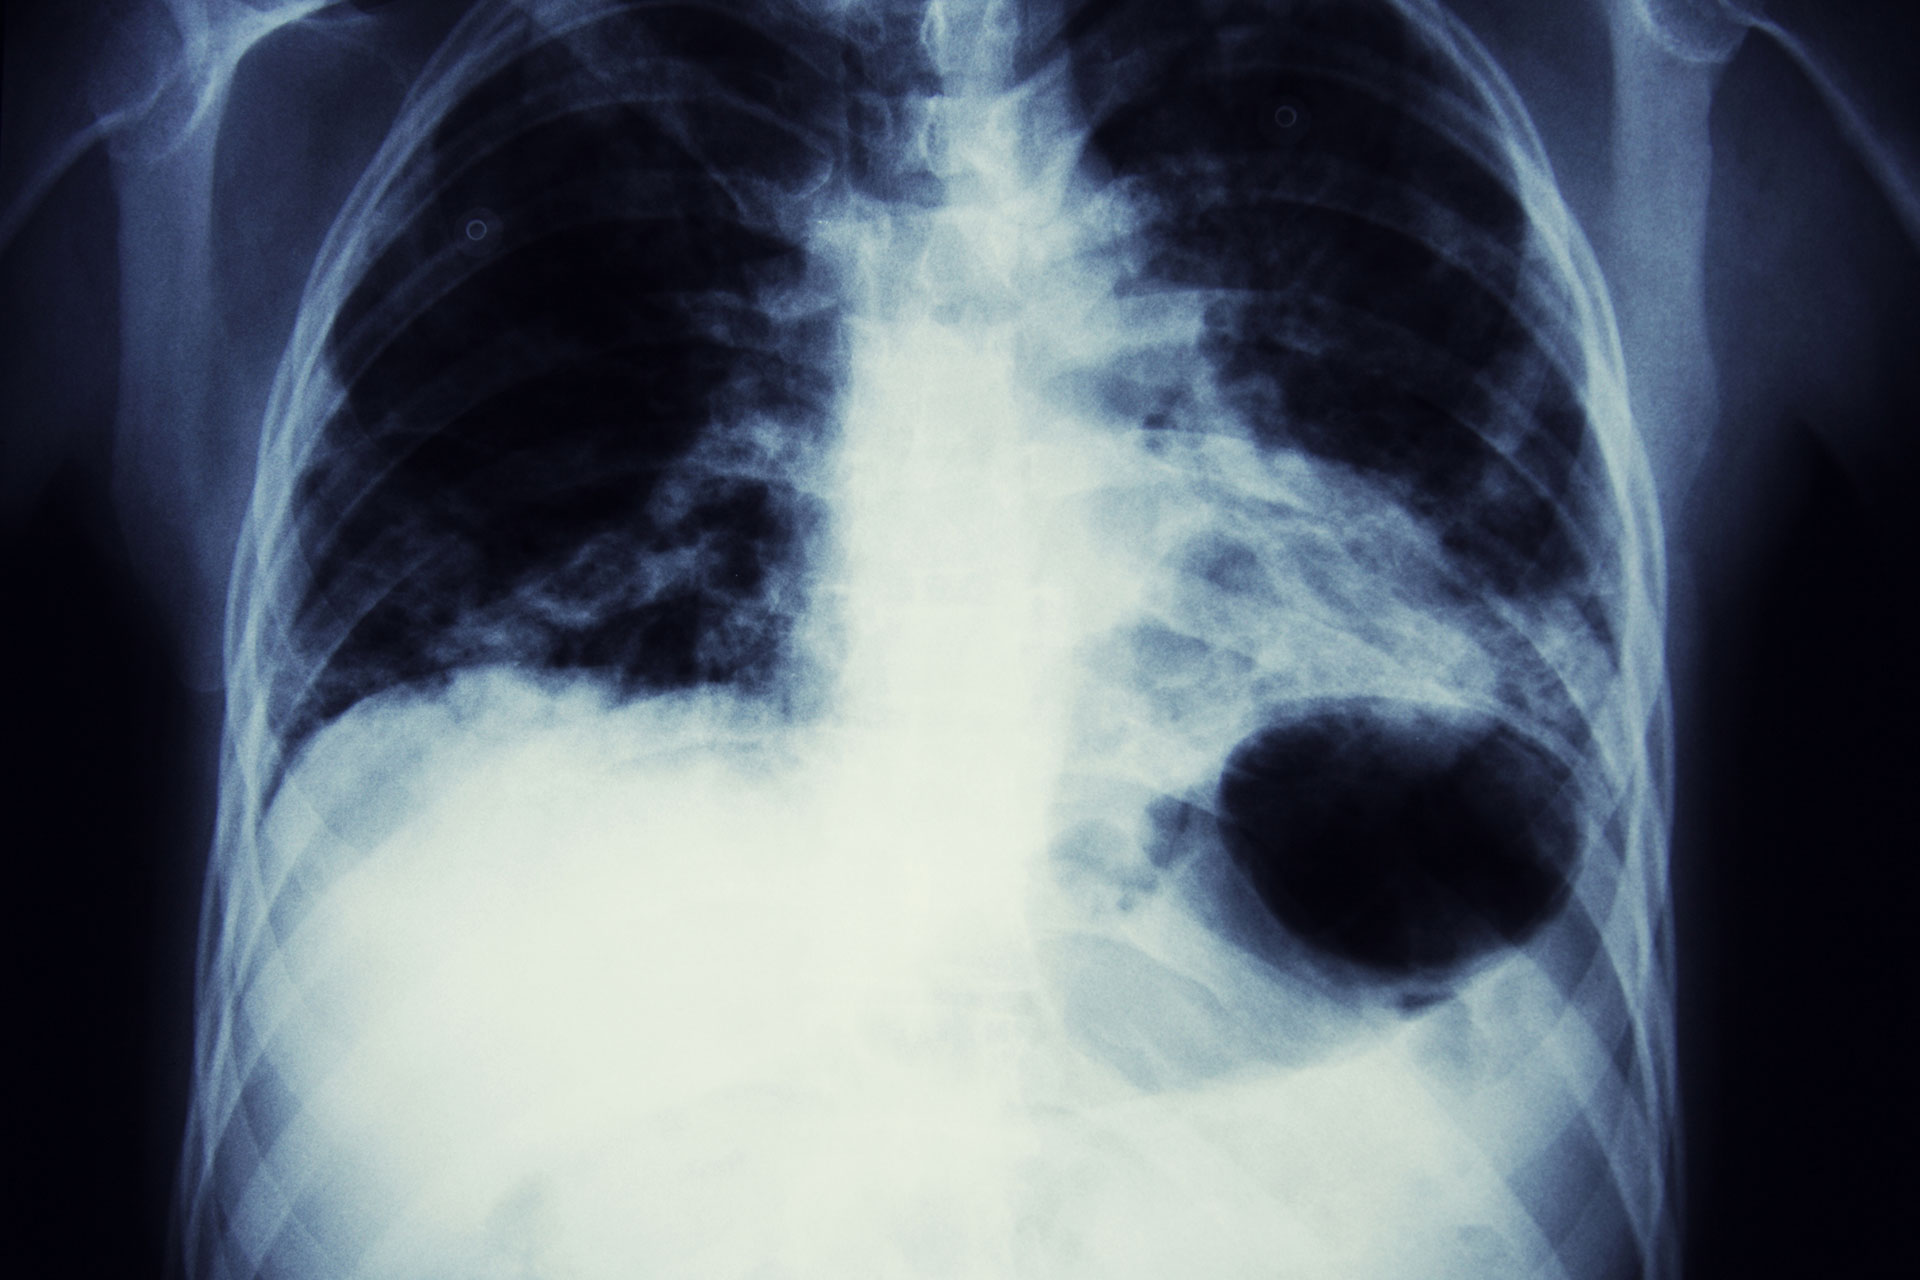

Pleural mesothelioma is diagnosed through imaging (MRI, CT scan, or PET). These tests determine the location of tumors and whether the cancer has spread.

- Imaging Tests: Chest X-rays can reveal lung abnormalities such as pleural thickening or effusion (fluid accumulation). Your healthcare provider may also request an MRI, CT, or positron emission tomography (PET) scan.

Although chest X-rays are commonly used to investigate lung concerns, they can only reveal abnormalities such as tumors, excess fluid, or thickened lung linings. To accurately diagnose mesothelioma, a biopsy is required.